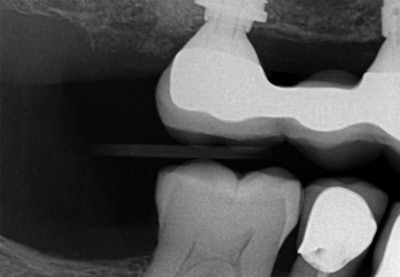

A 70-year-old patient presented to the dental practice for an emergency exam after experiencing pain around the peri-implant tissues of implant #5. On evaluation, sulcular pus and buccal edematous tissue were observed -- both associated with the implant in question. Following radiological studies of the affected area, implant #5 exhibited coronal bone loss and classic “cupping,” consistent with signs of occlusal overload. The patient received a diagnosis of peri-implant disease secondary to occlusal overload.

Because this was a complex case, an extensive treatment plan was developed, and advanced laser technology was used to maximize efficiency, effectiveness, and safety. Treatment consisted of debridement and disinfection with the Solea dental laser (Convergent Dental), a 9.3-µm CO2 laser, with guided bone regeneration.